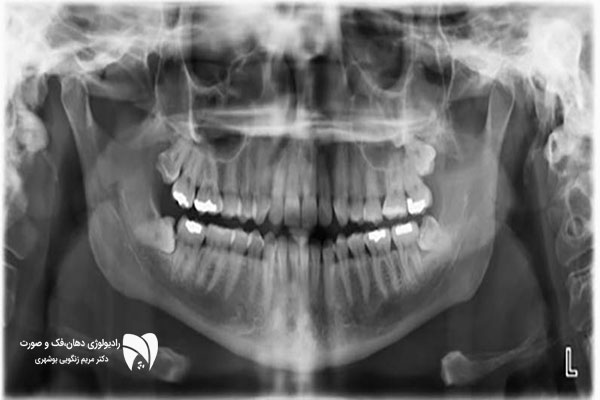

رادیولوژی دهان، علمی است که به تصویربرداری دهان، فک و صورت با استفاده از تکنولوژی پرتونگاری می‌پردازد. این تصاویر به دندانپزشکان کمک می‌کنند تا بیماری‌های دهانی را شناسایی کرده و روش‌های درمانی را برای آنها برنامه‌ریزی کنند.

از جمله بیماری‌هایی که با استفاده از تصویر برداری دهان قابل شناسایی می‌باشند، می‌توان به پوسیدگی دندان ها،  التهاب استخون و بافت های نگهدارنده دندان، عفونت دندان ها و بافت های اطراف آن ها، وجود شکستگی در دندان ها و استخوان های فکین، تومورهای دهان و فک و صورت و … اشاره کرد.

علاوه بر این، رادیولوژی دهان در بررسی مسائل مربوط به مفاصل فک و بافت‌های نرم صورت در شرایط خاص  نیز مورد استفاده قرار می‌گیرد.